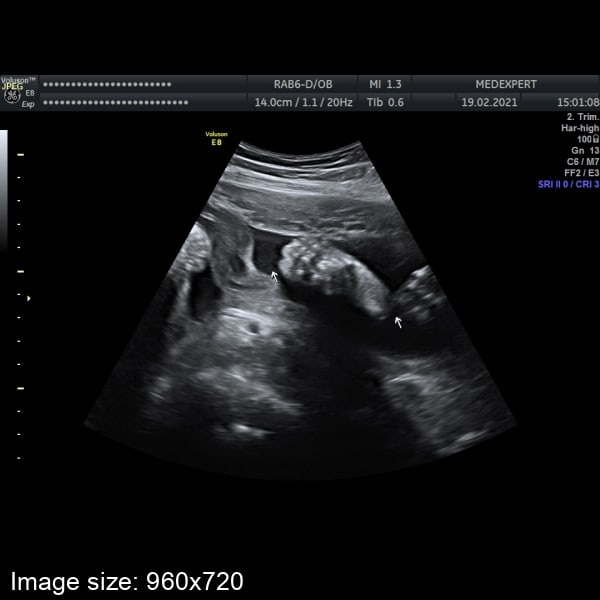

Вчера ходила на узи, сынок лежит головкой вниз, сердцебиение 134 ударов

Конечно чувствуется что малыш подрос, его вес ~1011гр.

Шла что бы увидеть личеко, но..все узи он прятался ручкой и не довал посмотреть 🤭